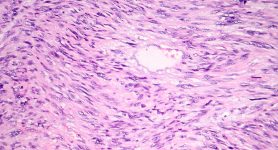

Leiomyosarcoma is believed to originate in the body’s smooth muscles, including the uterus, the intestines, stomach, bladder and blood vessels. Since smooth muscle is present throughout the body, leiomyosarcoma can occur anywhere in the body.

Leiomyosarcoma is a rare type of cancer that falls into the category of sarcomas, which generally arise from connective tissue. Leiomyosarcoma generally forms in the smooth muscles of the body.